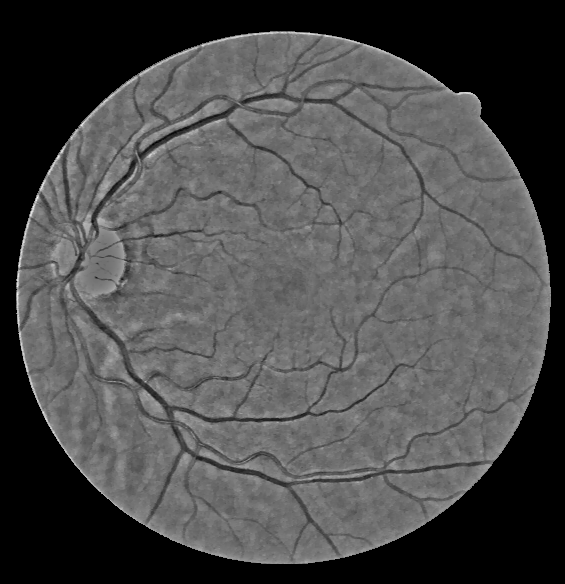

Base Layer, Detail Layer and Noise layer respectively. Base layer's lumination is corrected, detail layer is enhanced. Noise is discarded.

Base lumination correction

For illuminant correction, first the RGB space is converted to HSV space and V layer is extracted as luminance information, denoted as $L_{in}(x,y)$. Correction is done by the following equation, where n is the contrast enhancement parameter. It is set to 1 for all experiments given. \begin{equation} L_{out} = \frac{L_{in}^n}{L_{in}^n+\sigma_g^n} \end{equation} Visual adaptation level is determined by $\sigma_g$,which is a global adaptation level estimated from the whole luminance image from the equation below: \begin{equation} \sigma_g = \frac{M_g}{1+exp(S_g)} \end{equation} where $M_g$ and $S_g$ are the mean and standard deviation of the entire $L_{in}$ respectively. Finally, corrected base is found out by transferring the HSV space back to RGB space.

Base Layer and lumination corrected base